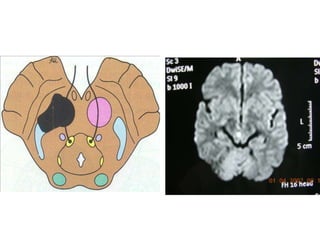

Pons-Lower

Medial pontine syndrome – occlusion

of paramedian branch of basilar artery

A.IPSILATERAL

1.Gaze paresis

2.Cerebellar signs

B.CONTRALATERAL

1.Hemiparesis

2.Hemianaesthesia

Lateral pontine syndrome-occlusion of

anterior inferior cerebellar artery

1.LMN VIIth nerve palsy

2.Gaze palsy

3.Deafness,tinnitus

4.Cerebellar signs

1.Impairment of pain and

temperature on the

body